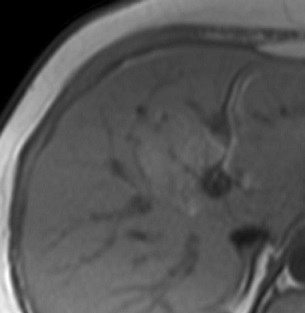

Image IRM de steatose fu foie

: Image de

hyperintense sur T1 et hypointense surT2 . L'infiltration graisseuse du foie provoque une diminution de

l'attenuation du parenchyme du foie . Sur le foie normale le

signal du parenchyme hepatique est similaire sur toutes les

images "in phase " et "opposed phase " . Dans steatose du

foie le signal du foie est hyperintense relative avec la rate (

T1 in phase ) et a opposed-phase , par la chute de

signal , image du foie est hypointensite ,

Image ỈRM normale du foie en

T1 coupe axiale .Image du foie est

hyperintense que la rate |

T2 coupe axiale . Le parenchyme du foie est moins intense que

la rate . |